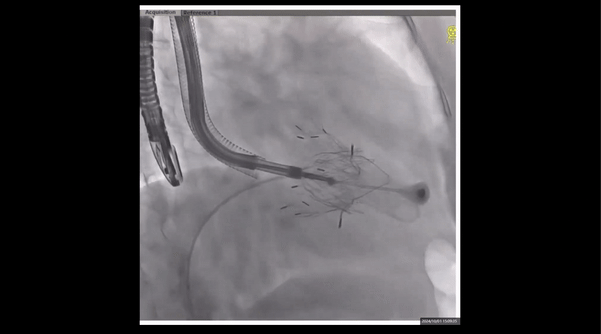

術前右室造影

夾持件位置確認

室間隔位置確認

瓣膜釋放

我們可以看到整個手術過程中,LuX-Valve Plus輸送系統的進入是非常順滑的,并且該病例巨大的瓣葉間隙,對于傳統的TEER療法和環縮術式是非常大的挑戰,因此三尖瓣介入置換是非常好的選擇。術中王焱院長團隊通過多次的人工瓣膜軸向調整,取得了非常好的封堵效果。室間隔錨定的設計也非常的巧妙,通過非徑向支撐的方式解決了三尖瓣假體瓣膜錨定的難題。再次恭喜王焱院長團隊順利完整這臺挑戰性的手術。